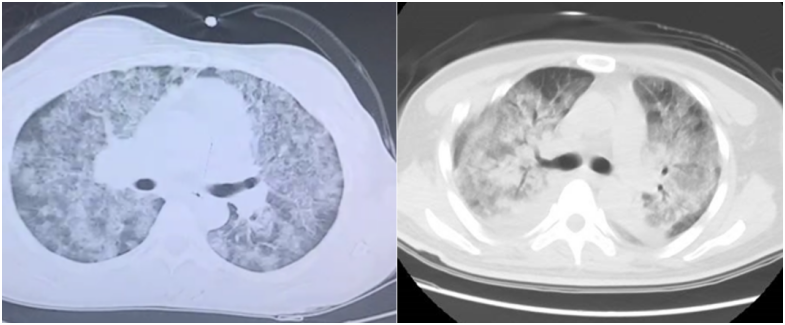

患者,女,50岁;活动后喘息20天,加重伴发热3天,2021年11月19日转入我院。入院胸部CT显示:双肺实变,磨玻璃影(图1)。11月24日复查胸部CT可见病变进展迅速(图2)。予患者气管插管机械通气、俯卧位等,呼吸衰竭未见改善。遂于11月25日启动VV-ECMO(转速2860 rpm,流量4.5 L/min,氧浓度100%)。追问病史:患者入院前1月有活动后气促症状,自觉全身不适,近2年有眼干、口干不适。进一步检查发现,ANA反应阳性(+),ANA核型为胞浆颗粒型(异常);抗SSA/Ro抗体阳性(++)、抗Ro-52抗体阳性(+++)。诊断:急性间质性肺炎(AIP);Ⅰ型呼吸衰竭;混合性结缔组织病。治疗:VV-ECMO+呼吸机辅助通气+俯卧位通气、激素(甲强龙80 mg×7天,60 mg×3天,40 mg qd)、免疫抑制剂(环磷酰胺400 mg qd×3天)、抗感染(哌拉西林他唑巴坦4.5 g q12h+莫西沙星0.4 g qd+氟康唑氯化钠注射液20 mg qd)、抗凝等。在随后的一段时间内,患者影像学改善不明显(图3)。直至12月20日,复查胸部CT可见患者肺部病变较前明显吸收(图4)。2021年12月31日VV-ECMO撤机后,继续气切呼吸机辅助通气,甲强龙40 mg qd抗炎治疗,继续抗感染治疗,2022年1月7日脱机,1月21日气管封管,1月26日出院。后续治疗:强的松25 mg qd,环磷酰胺600 mg q2w×4次,序贯吗替麦考酚酯0.5 g bid。重症间质性肺疾病(ILD)在诊断方面需要考虑以下问题:是ILD吗?是哪种ILD?严重程度如何?在治疗方面,除了生命支持(呼吸支持重点)和病因治疗,并发症的处理也至关重要。重症ILD的诊断包括两方面,一方面是通过影像学、病史+临床表现、BALF-NGS、实验室检查、肺活检等对ILD进行诊断;另一方面涉及重症,患者多面临呼吸衰竭甚至多器官衰竭,因此时间更加紧迫。在ICU内最常见的重症ILD包括:特发性肺纤维化急性加重(AE-IPF)、自身免疫相关性ILD、肿瘤治疗相关性ILD、隐源性机化性肺炎(COP)、AIP、过敏性肺炎(HP)、急性嗜酸性粒细胞性肺炎(AEP)、药物相关ILD等。在影像学方面,最易导致重症的类型有弥漫性磨玻璃影和实变影。最常见的鉴别诊断就是重症肺部感染。表现为弥漫性磨玻璃影或实变影的ILD较为多见,例如:HP、嗜酸性粒细胞性肺炎(EP)、结缔组织病相关间质性肺病(CTD-ILD)、非特异性间质性肺炎(NSIP)、脱屑性间质性肺炎(DIP)、淋巴细胞性间质性肺炎(LIP)、机化性肺炎(OP)、AE-IPF、肺泡蛋白沉积症(PAP)、肺泡微结石症、结节病、弥漫性肺泡出血综合征、肺水肿等。而很多感染性疾病影像学也可表现为磨玻璃影,例如:卡氏肺孢子菌肺炎(PCP)、病毒性肺炎、巨细胞病毒性肺炎、支原体肺炎。尽管如此,ILD也有部分影像学具有特征性,可以被识别。图5左表现为肺陷闭,也称为“猪头肉冻征”,这是典型的亚急性HP的影像学特征。图5右表现为弥漫性磨玻璃影,但以肺门向外扩展,外面有肺大泡,这是典型的PCP表现。临床上多见自身免疫性疾病导致的ILD,此类疾病也具有共同的特征,例如双肺弥漫,病理方面以NSIP或OP为主要特征。但也有部分患者可以出现弥漫性肺泡损伤(DAD)特征。如图6所示,左图为ANCA相关性血管炎,右图为MDA5相关性间质性肺病。因此,一定要警惕容易发生这种病理改变的自身免疫性疾病。